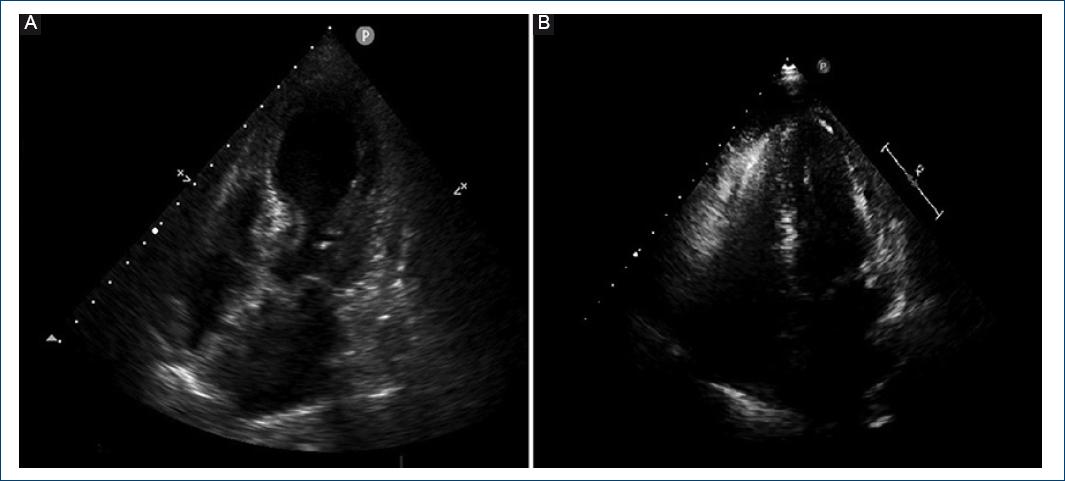

Figure 1 A: Apical window four-chamber transthoracic echocardiography performed in systole in the acute phase; akinesia of all apical and medial segments with basal segments hyper-contractility is observed. B: Apical window four-chamber transthoracic echocardiography performed in systole in the subacute phase, where contractility segmental alterations are not observed.

During the 1st day of ICU stay, slight crackles were documented in both lung bases, and T-wave inversion in the entire precordial series was observed on the surface electrocardiogram. In addition, myocardial damage markers (high-sensitivity troponin T, 154 ng/dL and creatine kinase, 43 U/L) elevation was detected, together with NT-proBNP increased values to up to 24,980 ng/L. Although the patient experienced no chest pain anytime, an urgent echocardiogram was performed, which revealed slight left ventricular hypertrophy with moderate left ventricular systolic dysfunction (calculated ejection fraction: 35-40%) due to akinesia of all apical and medial segments with basal segments hypercontractility (Fig. 1A). In view of these findings, an urgent coronary angiography was requested, which showed that epicardial coronary arteries were free of angiographic lesions (Figs. 2A and B).

Good respiratory evolution allowed early extubation at 36 h. Neurological workup was completed with a chest CT, which did not show thymus alterations that justified the episode. Control transthoracic echocardiography at 10 days indicated left ventricular systolic function normalization (75% ejection fraction) and absence of segmental contractile alterations (Fig. 1B).